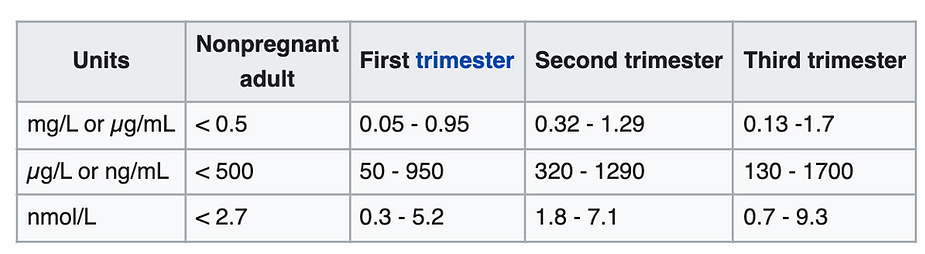

In this podcast, we talk with Dr. Robert Young who explains the significance of the D-dimer blood test as it relates to Covid-19 disease, pathological coagulation and blood clots leading to hypoxia and death. Click on the link below or any of the diagrams to listen and learn more about the D-dimer blood test and pathological blood clotting.

Understand Why Blood Clots Form Inside the Blood Vessels!

Read Dr. Robert O. Young’s Peered Review Scientific Research Article Published in the International Journal of Vaccines and Vaccination on Pathological Blood Coagulation! (2016)

Pathological Blood Coagulation and the Mycotoxic Oxidative Stress Testing, Young RO (2016) Pathological Blood Coagulation and the Mycotoxic Oxidative Stress Test (MOST). Int J Vaccines Vaccin 2(6): 00048. DOI: 10.15406/ijvv.2016.02.00048